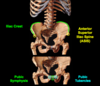

What are the landmarks on ilium and pubis?

Landmarks on the ilium:

- Iliac crest (at L4 vertebral level)

- Anterior superior iliac spine (ASIS)

Landmarks on the pubis:

- Pubic symphysis (at the midline where the two pubic bones meet)

- Pubric tubercles (prominances lateral to public symysis)